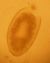

寄生虫图片-肝吸虫

图片尺寸600x862